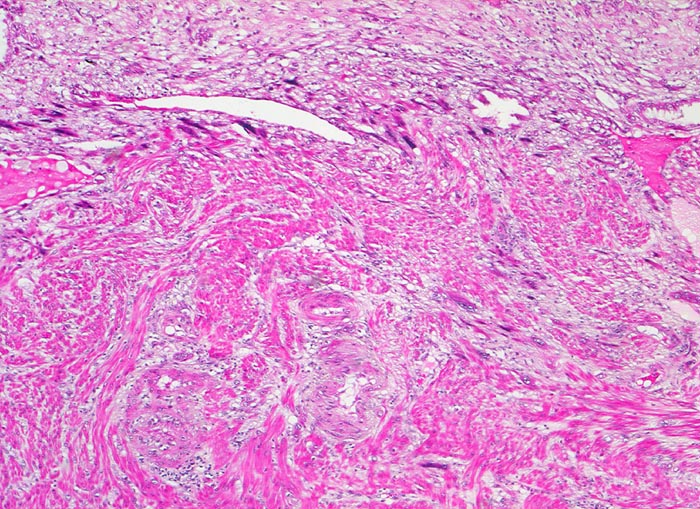

Morphologische Merkmale:

• Myometrium bedeckt von dezidualisiertem Endometriumstroma der Dezidua basalis.

• Invasion des Myometriums durch intermediären extravillösen Trophoblast.

• Fibrinoidschicht.

• Chorionzotten, ein Teil davon verankert mit dem dezidual transformierten Endometrium = Dezidua basalis (Haftzotten).

• Choriondeckplatte.

• Rechts oben Anteile des Chorion laeve.